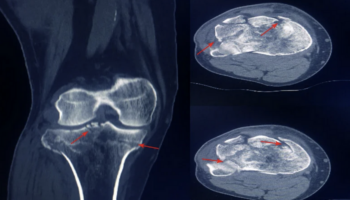

The patients underwent surgical repair of a periarticular tibial fractures (tibial plateau or pilon) between June 18, 2021, and December 12, 2024, at 39 trauma centers in the US.